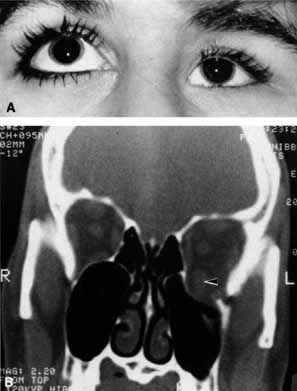

Anosmia caused by damage of cranial nerve I may be a helpful symptom of ethmoid or sphenoid sinus tumors invading the orbit (Fig. 20).44 Olfactory groove meningiomas and esthesioneuroblastomas may also present with anosmia prior to developing vision loss.45 Trauma that involves the orbit and is associated with anosmia should be considered a basilar skull fracture with potential for cerebrospinal fluid leak until proven otherwise (Fig. 21).

Fig. 20 A 13-year-old child presented with a 2-week history of sinusitis and anosmia. Her visual acuity decreased to to 20/400 1 day prior to admission. Computed tomography shows a large ethmoid tumor extending through the cribriform plate and optic canal. A rhabdomyosarcoma was diagnosed by biopsy.

Fig. 21 A 21-year-old man sustained a skull fracture from a motor vehicle accident 2 months prior to this examination. The patient describes anosmia since the accident. Computed tomography discloses a large medial wall orbital fracture extending through the cribriform plate (arrow). Orbital reconstruction was performed through a frontal craniotomy where dura was found incarcerated within the fracture. The orbital fracture was repaired by cranial bone grafting.